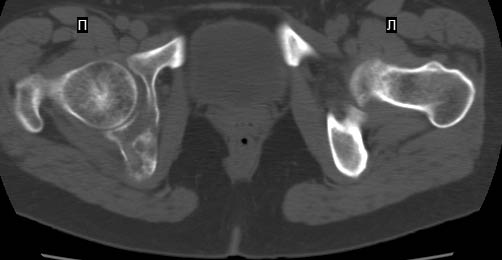

Сохранная по соматической патологии женщина ,47 лет. В 1996 г. установлен диагноз- cr левой молочной железы Т2N1Mo (2б)- проведено комплексное лечение- мастэктомия по Холстеду, ДГТ, 5 курсов ПХТ по схеме CMF. Сейчас менопауза уже 6-7 лет. В декабре 2004 года на профилактической остеосцинтиграфии с Тс99- выявлен единичный очаг повышенной фиксации препарата в зоне правой седалищной кости, рекомендована Рентгенография костей таза, выполнена- без патологии. УЗИ брюшной полости и Р-графия легких от конца апреля 2005 года - без патологии. Приблизительно 3 месяца назад появился болевой синдром в правом т/бедренном суставе с тенденцией к усилению. На рентгенограмме таза от мая 2005 года по заключению Рентгенолога очагов остеодеструкции не выявлено. Сегодня сделал ей Кт костей таза (картинки в приложении)- очаг деструкции в правой седалищной кости в зоне крыши вертлужной впадины.Что можно и нужно сделать? Жду советов, мнений, предложений по дальнейшей тактике ведения больной. С уважением, Корнев А.В.